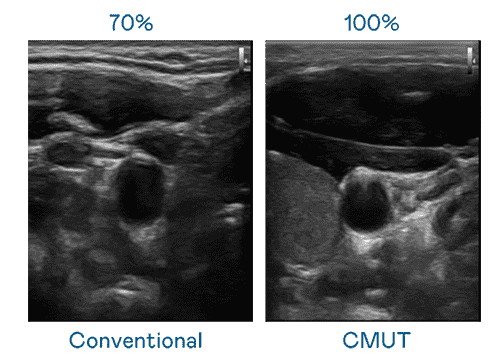

CMUT 技术是一种用电容式微机电元件来产生超音波讯号的技术。。。。与传统 PZT 压电式技术相比,,CMUT 频宽增加 30%,,,更宽频的超音波讯号让影像解析度大幅提升,,,,是实现高影像品质医疗超音波扫描、、促进精准医疗发展的关键技术。。。。

大频宽带来超清晰影像

超音波影像的解析度高低,,,,首先取决于探头能发出的讯号频宽。。。NG大舞台 CMUT 可提供高清晰的超音波讯号,,,,提供高频宽、、、高灵敏度、、、影像纹理细节更高的超音波影像,,,协助医护人员缩短影像判读时间及利用精准的医疗影像进行诊断。。。